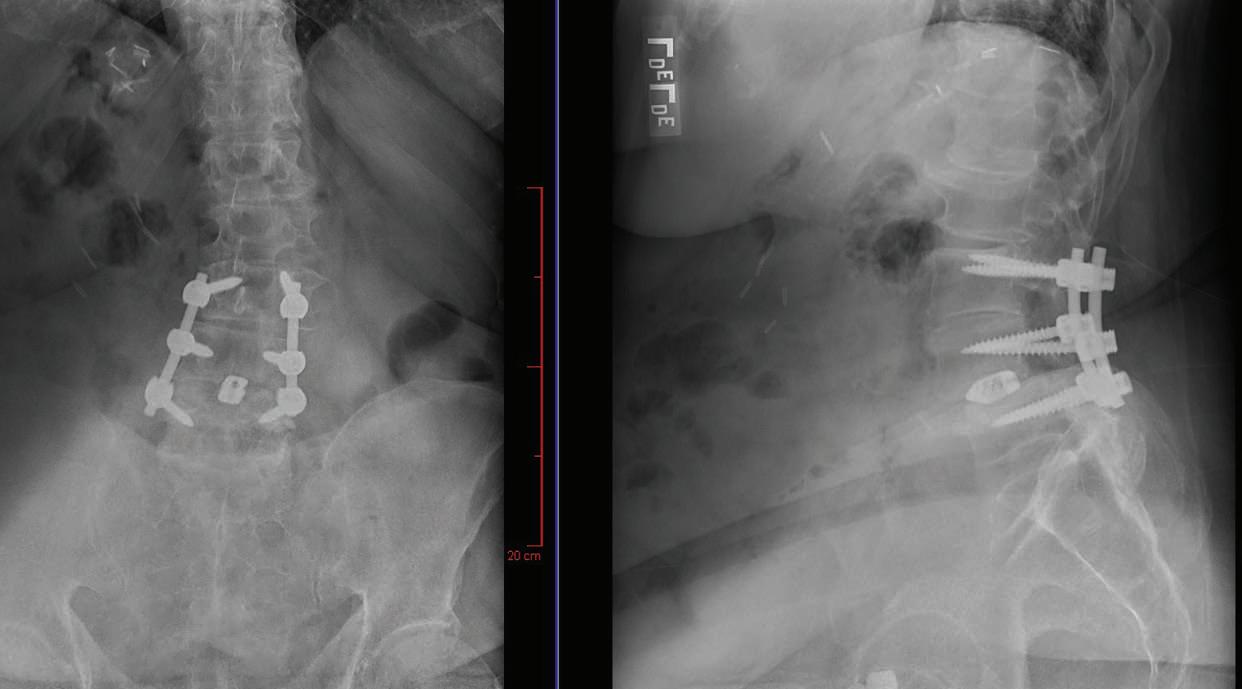

It was time to consider another step: surgery to fix any structural problems. An MRI and X-ray provided a clearer picture of what was going on. Peter’s spine showed signs of severe spinal stenosis. This condition occurs when spaces in the spine become narrowed due to factors such as injury or arthritis, placing pressure on nerves running through the spinal canal.

Matthew McDonnell, MD, a boardcertified orthopedic spine surgeon at RWJUH in New Brunswick, saw Peter’s case as urgent. “The steps we normally start with for symptomatic spinal stenosis—physical therapy, medication, epidural injections—had already been attempted,” he says. “Surgery to fix the structural problem was clearly necessary.”

first performed a laminectomy to remove bone and open the spinal canal, creating more room and easing painful pressure on Peter’s nerves. Dr. McDonnell then also addressed spinal instability due to arthritis by performing a fusion in which the spine was shored up using materials such as screws, spacers and bone grafts.

POST-OP FRONT-TO-BACK AND LATERAL X-RAYS PRE-OP MRI SIDE AND CROSS-SECTIONAL VIEWS